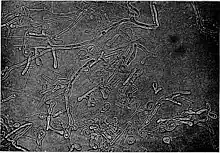

Blastomyces is a genus of fungi in the order Onygenales. Species are known human pathogens and show thermal dimorphism, converting from hyphal states under saprobic conditions to yeast-like states under pathogenic conditions. They are the causative agents of blastomycosis, a systemic mycosis in immunocompromised patients.[1][2]